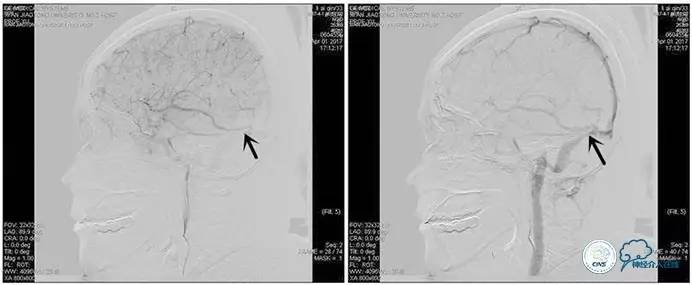

术中造影

5ml/s,总量8ml,压力100~150

右侧ICA正位

右侧ICA侧位

右侧ICA斜位

左侧ICA正侧位

右侧VA正位

左侧VA正侧位